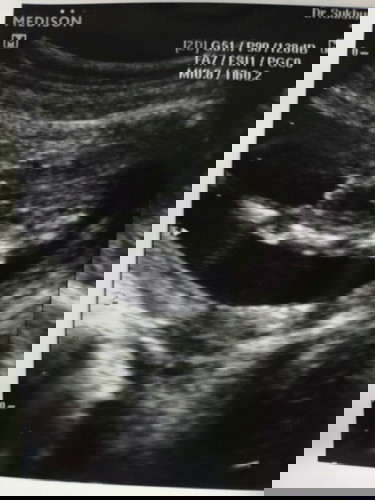

น้อง ญหรือช คะ แม่ๆช่วยดูหน่อย 15+4wค่า หมอยังไม่คอนเฟิร์ม

น่าจะผู้ชายนะคะ

ชายค่ะ

ชาย